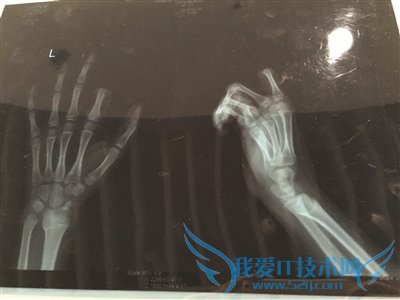

当时,小朋手里正拿着叉子在叉土豆泥吃,听了爸爸训斥的话后,立马就炸毛了,放下手中的叉子,转身就拿起了身后矮桌上的菜刀,朝着自己的左手切下去,当场,食指的两个指节就掉了下来。

手术历经3个多小时。若能顺利度过一个星期的危险期,接上去的手指便能成活。

午1点不到,小朋便被推进手术室做准备,下午4点左右,小朋才被推出了手术室,转入病房。不幸中的万幸,经过三个多小时的手术,小朋的手指被暂时接上。

外科主任周荣说:“孩子年纪太小,血管也非常细,所以手术难度比较大,现在,手指已经被接上了,接下来便看他的恢复情况了。”

据周荣介绍,手术后,小朋的手一定不能乱动,否则很容易造成血管堵塞。如果小朋的配合程度高,顺利度过了一个星期的危险期,接上去的手指成活了,那么,这次事故对小朋今后生活的影响应该不大。